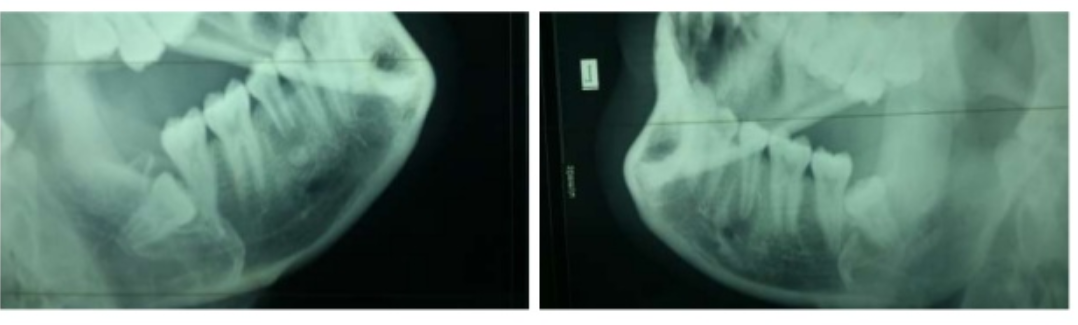

- Kết quả chụp tách được xương hàm bên cần chụp, thấy được khớp thái dương, xương hàm dưới cần chụp

- Chất lượng tia trên phim rõ nét, độ tương phản cao, rõ ràng, tia vừa thì thấy rõ vân xương, bè xương, thấy được phần mềm, ti a non thì phim sẽ mờ, nhiều bóng phần mềm, tia già sẽ khiến phim đen, ít bóng phần mềm.